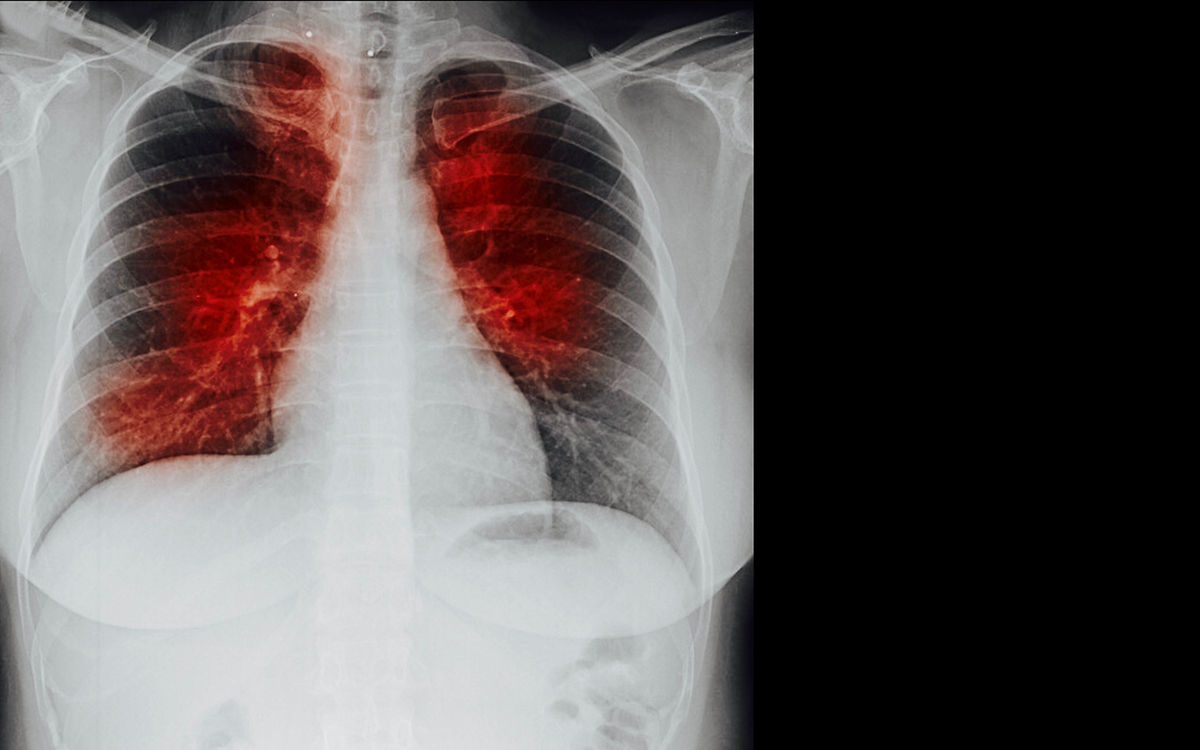

さらに重篤な合併症として深部静脈血栓症(DVT)があり、これは肺塞栓症(PE)※を引き起こす最も重大なリスク因子の一つです。

事実、腸骨大腿静脈に血栓が生じた患者の約半数が、程度の差はあれ肺塞栓も併発しており、肺塞栓は全入院死亡の約5〜9%を占めると報告されています[2]。

※肺塞栓症(はいそくせんしょう)は、足などの静脈でできた血栓が肺の血管(肺動脈)に詰まり、急激な呼吸困難や胸痛、失神を引き起こす命に関わる循環器の緊急疾患です。